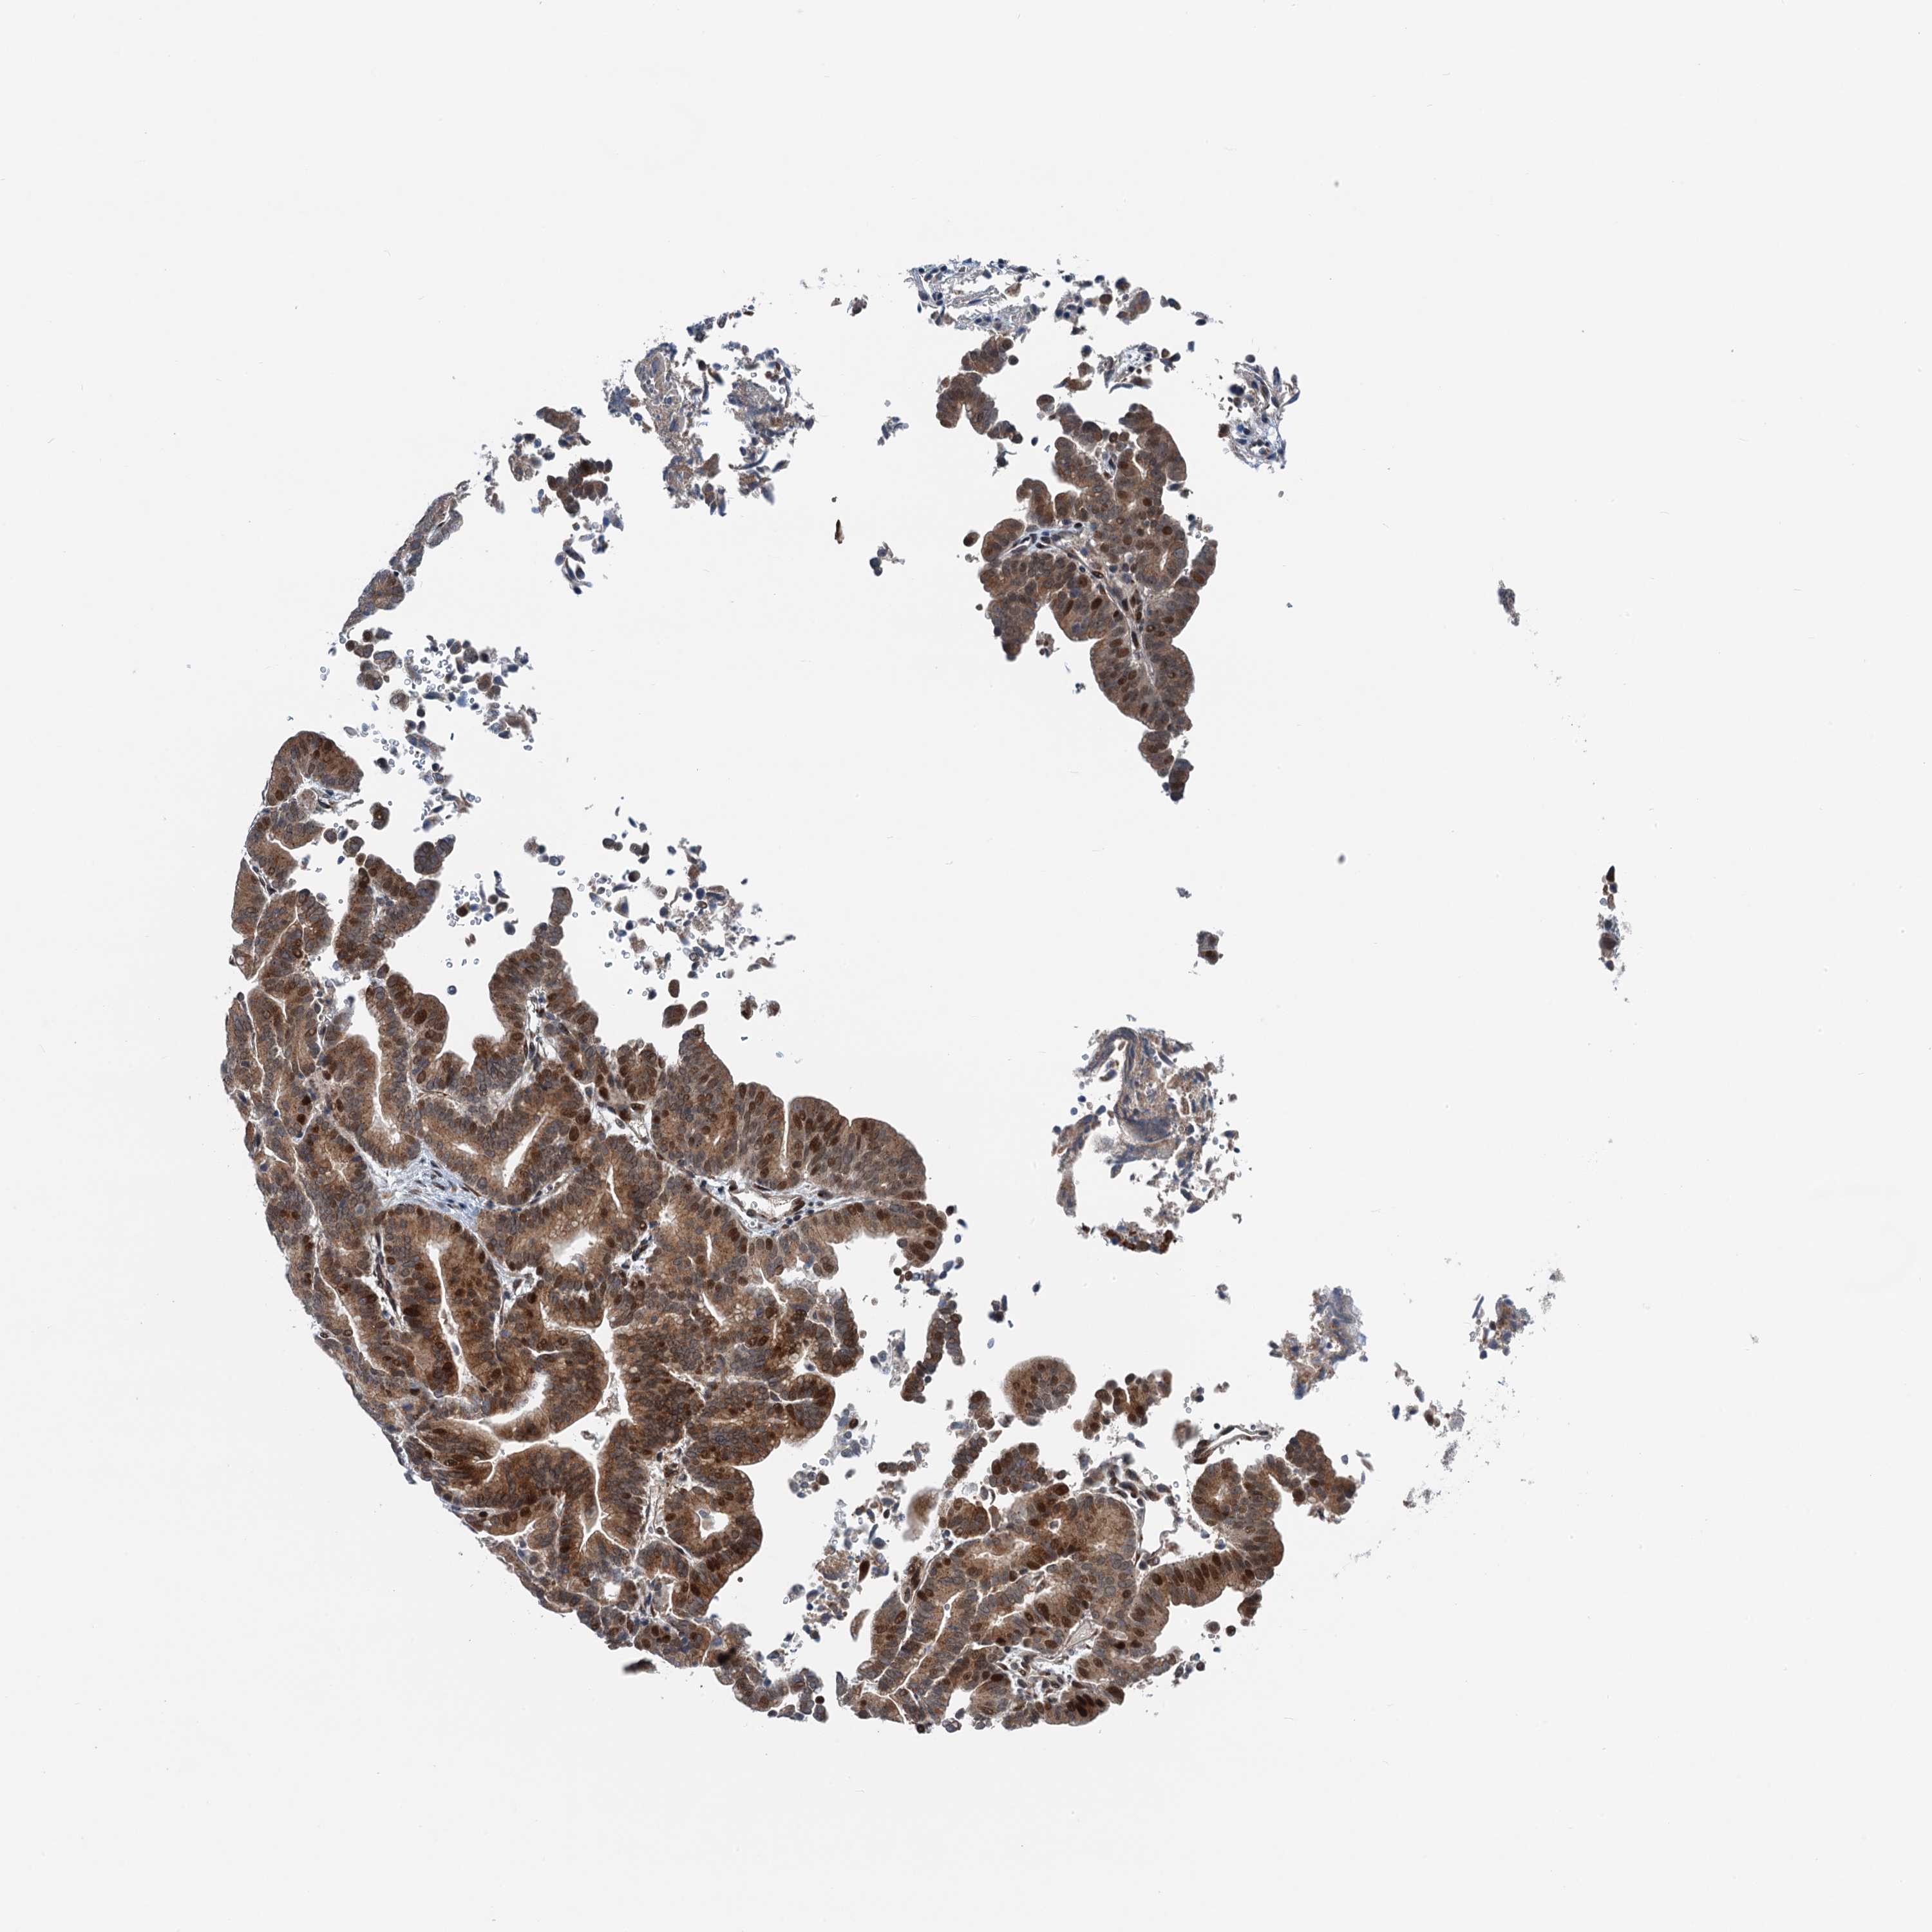

LIVER CANCER - Protein expressioni

A mouse-over function shows sample information and annotation data. Click on an image to view it in a full screen mode. Samples can be filtered based on level of antibody staining by selecting one or several of the following categories: high, medium, low and not detected. The assay and annotation is described here.

Note that samples used for immunohistochemistry by the Human Protein Atlas do not correspond to samples in the TCGA dataset.

Antibody stainingi

Antibody staining in the annotated cell types in the current human tissue is reported as not detected, low, medium, or high, based on conventional immunohistochemistry profiling in selected tissues. This score is based on the combination of the staining intensity and fraction of stained cells.

Each image is clickable and will lead to virtual microscopy that enables deeper exploration of all samples and also displays staining intensity scores, fraction scores and subcellular localization as well as patient and tissue information for each sample.

Antibody HPA040764

Staining

High

Medium

Low

Not detected

Intensity

Strong

Moderate

Weak

Negative

Quantity

>75%

75%-25%

<25%

None

Location

Nuclear

Cytoplasmic/membranous

Cytoplasmic/membranous,nuclear

Cholangiocarcinoma

Carcinoma, Hepatocellular, NOS